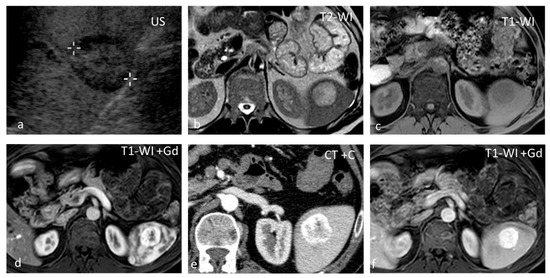

Hemangioma, although rare, is the most common splenic neoplasm and is found in up to 14% of patients at autopsy. It is formed by a proliferation of vascular channels, lined by a single layer of epithelium, and filled with blood. Hemangiomas are usually asymptomatic, solitary, or multiple. The natural course of hemangiomas is slow growth, and symptoms or complications, when present, occur late. Splenic hemangiomas may occur as part of generalized angiomatosis, as seen in Klippel–Trenaunay syndrome. Complications include rupture, hypersplenism, and malignant degeneration. Kasabach–Merritt syndrome, which involves the triad of anemia, thrombocytopenia, and coagulopathy, has been reported in patients with large hemangiomas [32]. Hemangiomas are round-shaped lesions with well-defined margins and a diameter <2 cm. Calcifications and cystic changes may be seen in up to 30% of cases. On US, hemangiomas have a variable appearance, being most commonly hyperechoic [32]. They appear hypoattenuating on non-contrast CT, hypo- to isointense on T1-WI, and hyperintense on T2-WI (Figure 6). Contrast enhancement can be immediate, homogeneous, and persistent or present as early peripheral enhancement with either uniform delayed enhancement or with fill-in and delayed enhancement of a central fibrous scar. Spontaneous rupture has been reported to occur in 25% of splenic hemangiomas, and treatment in such cases most often consists of splenectomy. In a study including 32 patients with splenic hemangiomas,11 of the patients had splenic lesions characterized as such based on their typical imaging findings on CT and US alone, while all were managed successfully with observation [33].

Figure 6.

Hemangioma. A well-defined isoechoic splenic lesion with a hypoechoic rim on US (a). The lesion appears hyperintense on T2-WI with a thin hypointense rim (b) and hypointense on T1-WI (c), demonstrating strong peripheral enhancement in the early phases post intravenous contrast administration both at MRI (d) and CT (e), and homogeneous delayed enhancement (f).